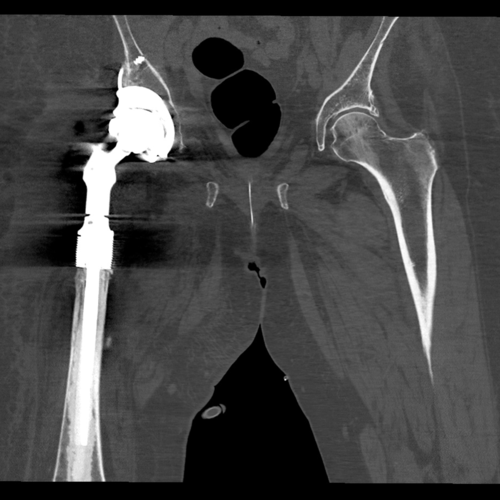

Post Operative radiographs from 6 months after the operation showing the METS proximal femoral replacement articulating with the custom Trabecular Titanium acetabular implant. Both components are well fixed and well positioned.

Post operative CT - This post-operative computer tomography scan shows the acetabular component with good contact to the host bone and a well-positioned proximal femoral replacement.